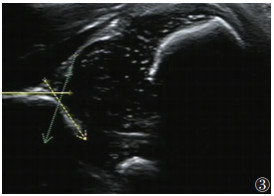

1.2 仪器与方法采用Siemens Acuson S2000超声诊断仪,高频线阵探头,频率4~9 MHz。超声检查均由具有5年以上工作经验的超声诊断医师完成。记录首次超声检查时双侧SCM厚度,计算双侧SCM厚度差值及厚度比率。应用Graf方法[15]测量基线、骨顶线及软骨顶线构成的骨顶角(α角)及软骨顶角(β角),并结合年龄对髋关节进行超声分型(表 1)。将患儿分成2组:合并DDH者为CMT+DDH组,不合并DDH者为CMT组,并对超声及临床相关资料进行分析。

| 表 1 Graf法髋关节超声分型 |